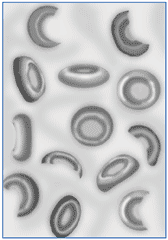

Гемолитическая анемия (лат. anaemia haemolytica от др.-греч. αἷμα «кровь» + λύσις «разрушение, растворение» + анемия) — групповое название редких заболеваний, общим признаком которых является усиленное разрушение эритроцитов, обусловливающее, с одной стороны, анемию и повышенное образование продуктов распада эритроцитов, с другой стороны — реактивно усиленный эритропоэз.

- Мембранопатии эритроцитов (нарушение строения эритроцитов):

- микросфероцитарная,

- овалоцитарная,

- акантоцитарная.